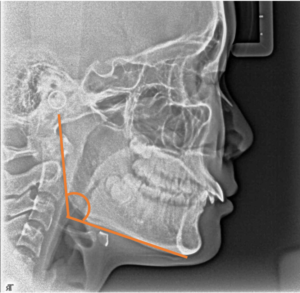

前回の開咬の話の時にも説明しましたが、過蓋咬合の原因も骨格や筋肉など、遺伝的な要素が強く(図6)、成長がある場合はできるだけ骨格的な問題を改善する装置(ヘッドギアやバイオネーターなど)で治療を行います(図7、8)。又、ユーティリティーアーチ(図9)を使用して上の前歯を鼻の方向に押し込むような力(圧下)をかけて深い噛み合わせを治します。

図6過蓋咬合になりやすい骨格(反時計回りに成長しやすい)